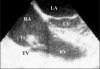

A 35-year-old woman with a previously repaired atrial septal defect was referred for preoperative evaluation before laparoscopic surgery. The patient was asymptomatic, and a transesophageal echocardiographic examination revealed a probable thrombus attached to the tricuspid valve. The patient's history included therapy with a gonadotropin-releasing hormone analogue and deep venous thrombosis five months earlier. The tricuspid valve thrombus disappeared after anticoagulant therapy. Warfarin was initiated for prophylaxis. During the follow-up, the patient was event-free during laparoscopic surgery and pregnancy (when warfarin was switched to acetylsalicylic acid) and gave birth to a healthy term baby. Because etiological investigations revealed no reason for the tricuspid valve thrombus, it was considered to be related to the procoagulant state induced by hormonal treatment. The patient was scheduled for close follow-up.